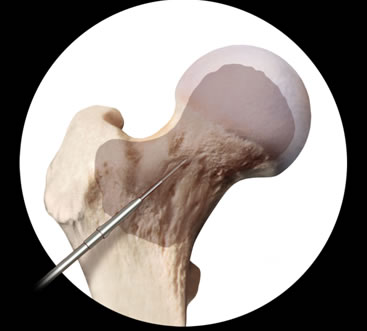

In tali condizioni, tramite una piccola incisione, utilizziamo l'infiltrazione percutanea di una alta concentrazione di MSC (fig. 3), ottenute dall'aspirato midollare da cresta iliaca. Questa metodica può invertire il processo patologico, ripristinando la popolazione cellulare necessaria alla rigenerazione delle strutture coinvolte dall'ischemia. È stato dimostrato come questa procedura riduca drasticamente la durata dei sintomi nei casi di edema transitorio e si suppone che possa ridurre i rischi di progressione verso quadri più avanzati di necrosi della testa del femore.